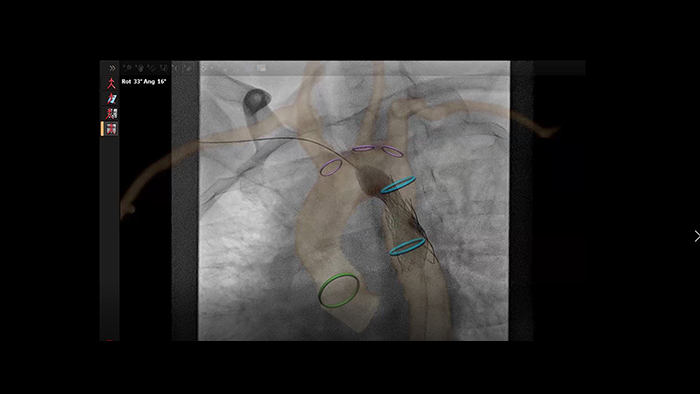

Automatic vessel analysis from rotational angiography with SmartCT

SmartCT live guidance